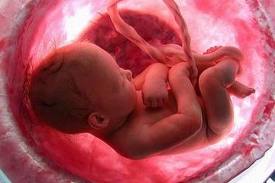

Il pancione è cresciuto ancora e non permette di vedere neanche i piedi. Il bambino pesa circa 2 kg ed è lungo circa 38 cm. Ogni settimana metterà su tra i 200 e i 250 gr e diventerà sempre più cicciottello. Le ossa cominciano a solidificarsi, esclusa la scatola cranica, che deve rimanere malleabile per permettere la nascita.

Il piccolo continua a crescere e dovrebbe pesare circa 2250 grammi, ma le stime del peso fetale sono variabili e oscillano di circa il 10% in più o in meno a quanto segnalato. Infatti, ora ci si basa su dei calcoli di equazioni matematiche partendo dalle misure ecografiche della circonferenza cranica, della circonferenza addominale e della lunghezza del femore che possono orientare sul peso, ma non darne la certezza.

Il peso del piccolo è arrivato intorno ai 2550 gr., è più rotondo, si muove in rapporto al poco spazio che ha a disposizione e il suo sistema neurologico è ben sviluppato.

Il bambino è arrivato a pesare circa 2750 grammi ed è lungo circa 48 centimetri. Il suo corpicino comincia a perdere la peluria e la vernice caseosa che l’ha ricoperto finora per proteggerlo dall’azione irritante del liquido amniotico. Queste e altre sostanze sono ingerite dal piccolo con il liquido e vanno a formare il meconio.